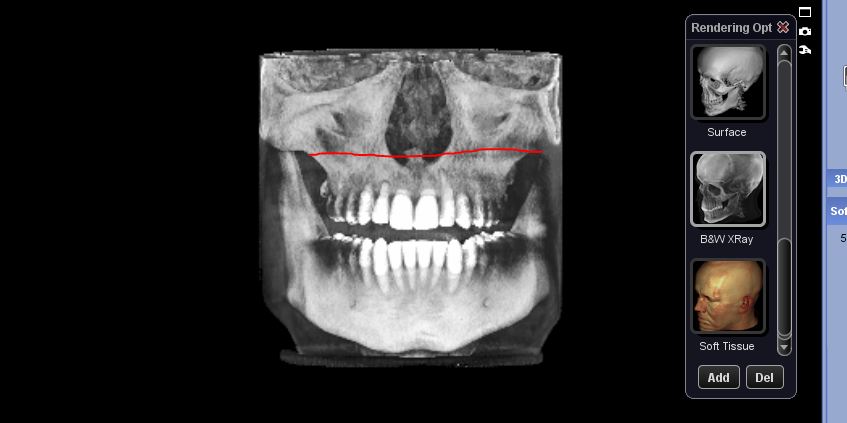

deformed maxilla, lopsided and short alveolar

Jaw Is small, maxilla too, palate seems not Wide and zygos flatbsd what is that?

PM for further assistanceJaw Is small, maxilla too, palate seems not Wide and zygos flat

Okay i mean, irl It can be different, here i see the bone irl there Is soft tissue, also its not that that bad i exagerated a bit.View attachment 4670693

i might get lefort 1 downgrafting and that would also probably fix asymmetry.

But yeah lefort 1 can Ascend you indeed